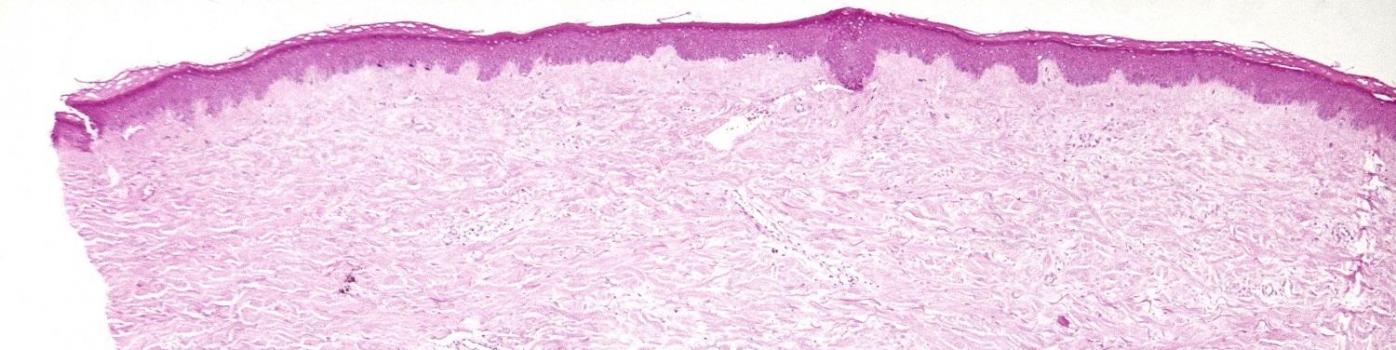

La sclérodermie est une maladie appartenant à la famille des connectivités, qui regroupe différentes maladies auto-immunes du tissu conjonctif. Elle concernerait entre 1000 et 1200 personnes en Suisse, plutôt des femmes (seuls 15 % d’hommes). Elle impacte la peau mais aussi, en fonction de son évolution, les poumons, le système digestif, le cœur, les vaisseaux sanguins ou encore les reins.

Les symptômes fréquents sont un épaississement et un durcissement de la peau, surtout du visage et des doigts. Le syndrome de Raynaud, caractérisé par une mauvaise circulation du sang dans les mains, est souvent un des premiers signes de la sclérodermie. Le Dr Iudici a mis en place une consultation de capillaroscopie, examen indolore qui, à l’aide d’un microscope, met en évidence les lésions dans les petits vaisseaux.